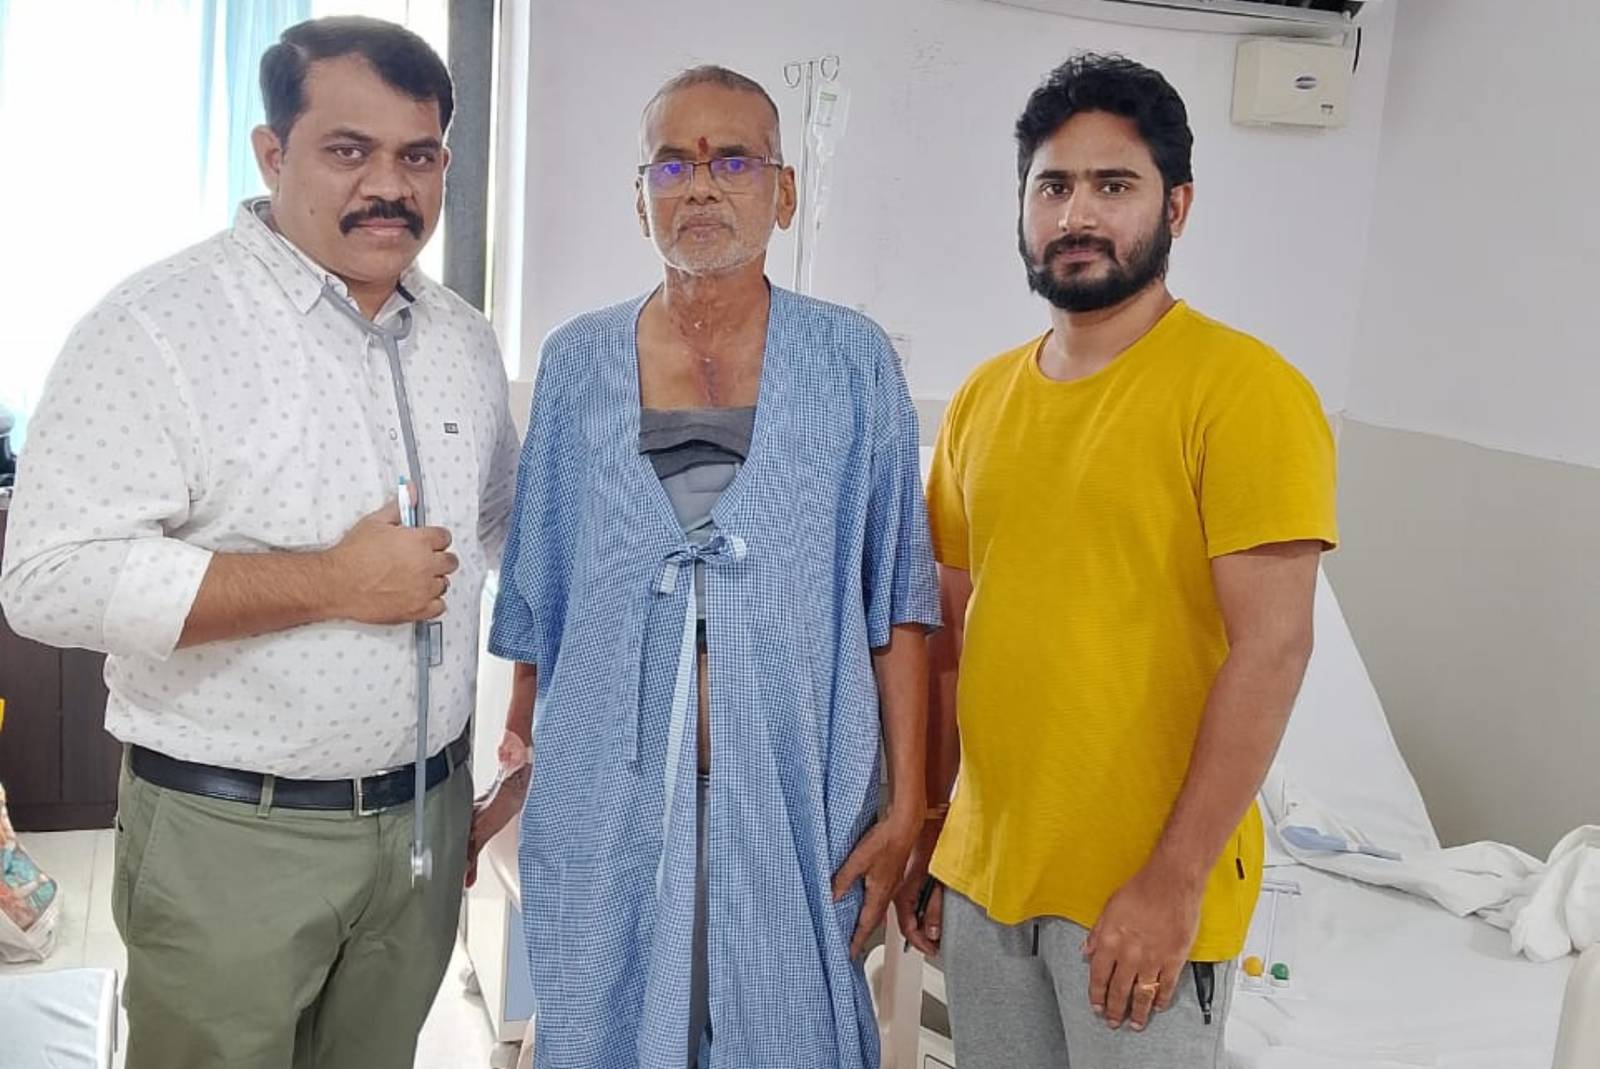

Dr. Jagannatha Raju is the best cardiologist in Vizag, offering expert heart care at Varma Hospitals.

With 20+ years of experience, he specializes in advanced diagnosis and treatment of heart conditions.

His dedication to patient well-being ensures high-quality and compassionate healthcare.

Trust Dr. Jagannatha Raju for the best cardiac care in Vizag.